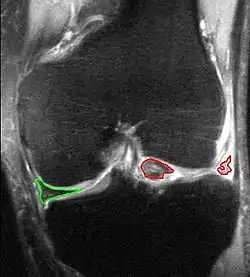

בשלב הראשון של תהליך האבחון של קרע במיניסקוס יתחיל מלקיחת ההיסטוריה הרפואית תוך התמקדות באזור הכואב וניסיון לאתר את המקור לכאב ולהבין מתי וכיצד החל, מהו סוג הכאב, מה מקל ומה מחמיר אותו ועוד. השלב השני הוא שלב הבדיקה הפיזית של המטופל בכלל, ומצב הברך בפרט. בשלב הזה יוערך מצבו הנוכחי של המפרק ולפי המצב תבחר דרך הפעולה הרצויה למטופל. בשלב השלישי המטופל יתבקש לעבור מספר בדיקות שתכלולנה תצפית על אופי ההליכה ו/או העמידה של החולה, בדיקות טווח התנועה של הברך, בדיקות אורתופדיות ובדיקות נוירולוגיות. חלקן יהיו בדיקות שטחיות כמו בדיקת טווח התנועה של הברך, אופי ההליכה והעמידה וכו', אך במידת הצורך יכול להיות שימוש גם בבדיקות הדמיה (בדיקות CT ו-MRI המספקת את התוצאות האמינות ביותר) ובדיקות מעבדה נוספות.

- MRI showing a buckle handle tear